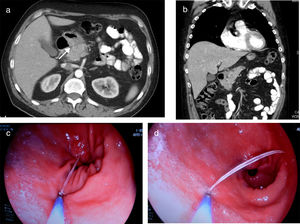

Computed tomography (CT) scan of thorax/abdomen showed inflammatory changes in the peripancreatic fat, and in the adjacent gastric antrum, pylorus and duodenal bulb. A linear image of at least 3cm was observed which, from the lumen of the antrum, was pointing towards the head of pancreas, with thickening of both structures (Fig. 1a and b). Performing gastroscopy we found an area of oedematous mucosa with fibrin at the roof of the pyloric antrum. Washing of the area revealed the tip of a trapped fish bone, which we were able to extract with forceps without incident (Fig. 1c and d).

(a and b) Images from the thorax/abdomen CT scan showing frayed edges and increased peripancreatic fat density, and of the adjacent gastric antrum, pyloric region and duodenal bulb, with linear image (arrow) of at least 3cm from the lumen of the antrum to the head of pancreas, with thickening of both structures; (c and d) gastroscopy images of the extraction of the fish bone with forceps.